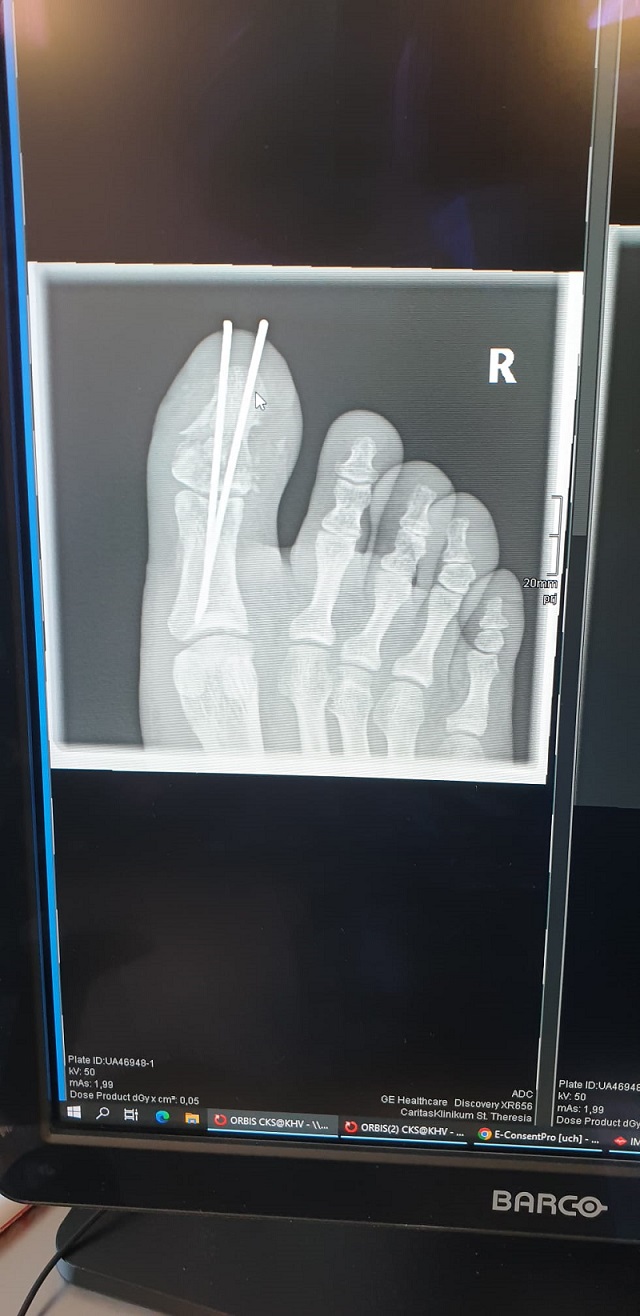

Das Ergebnis warrecht schnell durch den Turnschuih sichtbar. Also umgezogen und ins Krankenhaus gefahren. Diagnose offener Trümmerbruch im rechten großen Zeh, OP heute mittag.

Nun bin ich seit 2 Tagen zuahsue undhalte Ruhe. 6 Wochen, bis die Drähte wieder raus kommen.